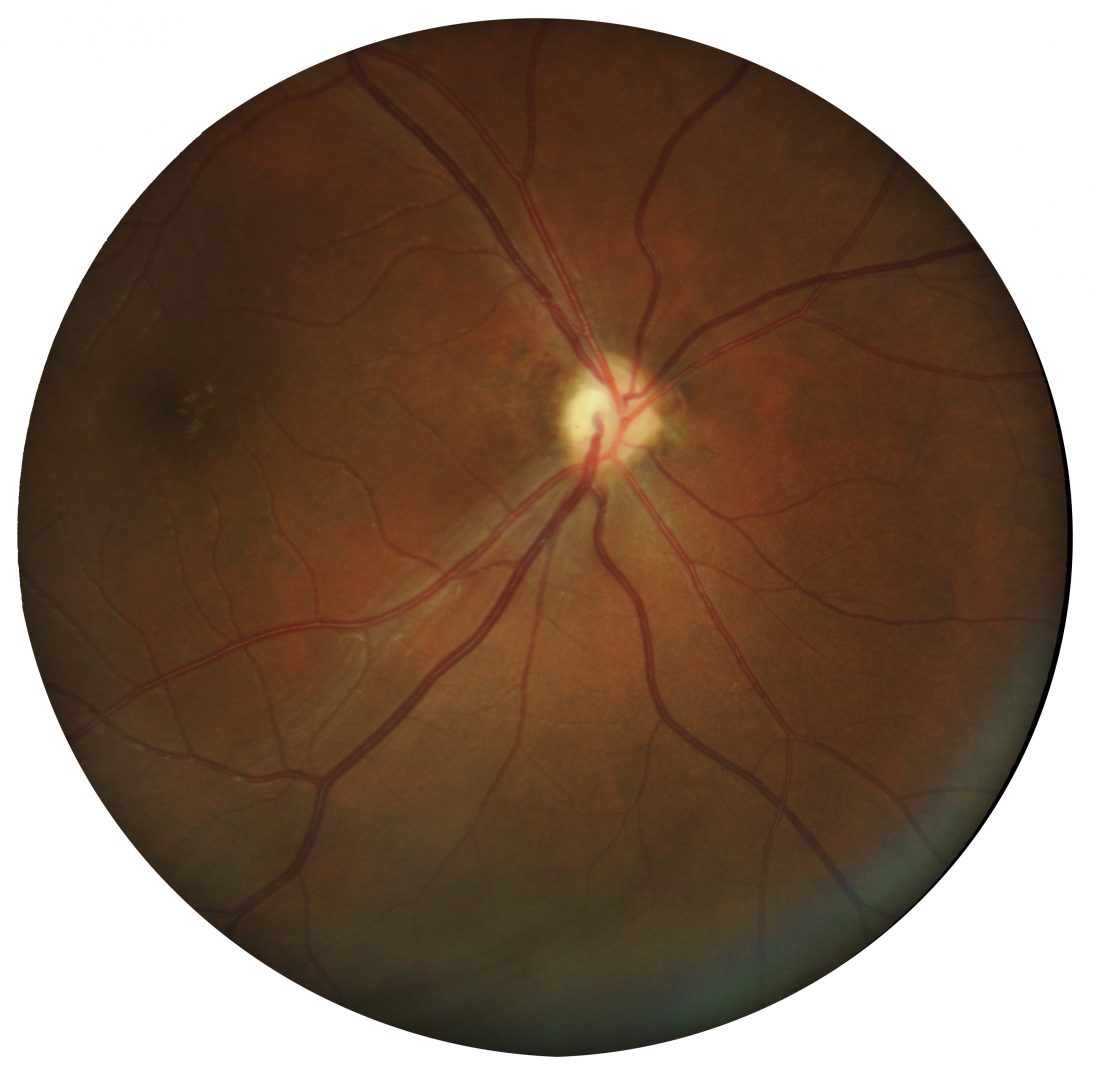

This condition is associated with a reduction in visual acuity that may range from light perception through to slightly sub-normal vision. Clinically, a very small optic nerve head is seen often surrounded by a ring of sclera.

Case 1: Bilateral optic nerve hypoplasia

A 53 year old Caucasian male with best corrected visual acuity of 6/30 (20/100) in each eye. He has had poor vision since birth.

Fundus photographs (right and left eye)